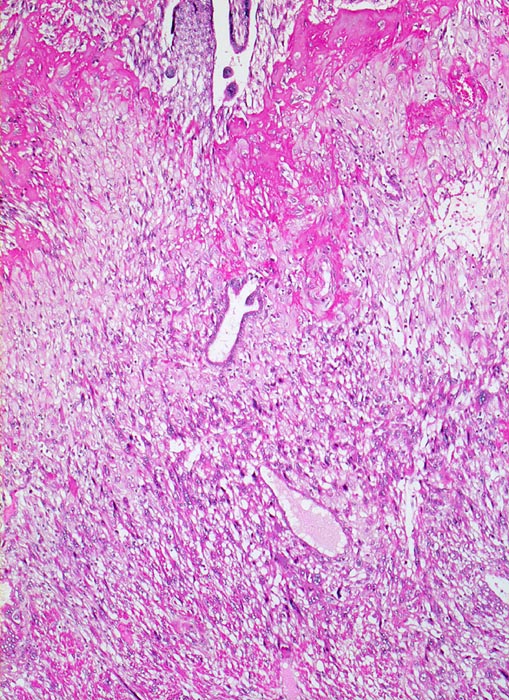

PathoPic – image database / PathoPic ID 5213 - Gravidität

Gravidität

Plazenta

Oben im Bild Anschnitte des proliferierten Trophoblast der Haftzotten. Daran angrenzend eine homogene rote Schicht von Fibrinoid und darunter die Infiltrationszone des intermediären extravillösen Trophoblast im Bereich der Dezidua. Die hellen blasigen Zellen entsprechen der Dezidua. Diese wird infiltriert von intermediären Trophoblastzellen mit dunklem Zytoplasma und grossen hyperchromatischen Kernen.

11. Schwangerschaftswoche. Normale Schwangerschaft

Histologie

50